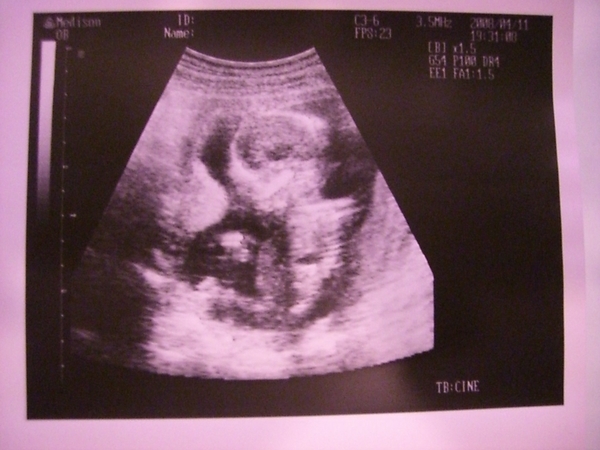

寶寶再過三天就滿四個月~

每次產檢總是期待與寶寶相見

看著他在羊水裡游來游去 過動的樣子 挺有趣

還看到他原本握拳的手 突然張開手掌

彷彿在跟我們 say "hello"

重點來了 我看到寶寶發亮的雙眼

就趕緊笑著問醫生:為啥我寶寶眼睛會發亮 怎像外星人

醫生說那是"寶寶的眼框 且是因為超音波照出來 所以會覺得眼睛發亮"

醫生說我寶寶很健康喔!!

可是因為還太小 看不出是男是女

我好想知道是男是女 因為醬我才知道如何稱呼我的寶寶

下個月就知道了~~期待中^^~~